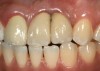

The crown and screw-retained custom abutment were removed, and a surgical cover screw was placed into the implant, thereby allowing spontaneous gingival augmentation in situ (Figure 33 and Figure 34). Note that the lingual aspect of the implant site was significantly more coronal than the labial aspect, which was positive because the defect would be limited to a facial–lingual defect. A fixed RBR bridge was cemented on the adjacent teeth and used as a tooth-supported transitional provisional restoration (Figure 35). A few weeks were allotted to let the soft tissue heal and migrate around the cover screw (Figure 36) to see if there would be complete coverage, thereby allowing a soft-tissue augmentation procedure to be performed with primary flap closure as in clinical scenario No. 2. The major obstacle in achieving a positive tissue response was that the implant depth was also deficient because the implant–abutment connection was at the level of the free gingival margin. It was decided that the best treatment option would be to remove the implant. A high-powered reverse-torque device (Fixture Remover Kit, NeoBiotech, www.neobiotechus.com) was used to remove the implant atraumatically (Figure 38 through Figure 41). The implant socket was allowed to heal for several months not unlike an extracted tooth (Figure 42). A new implant was placed in a better position from both a restorative and esthetic perspective (Figure 43), and after a few months of healing, a new crown was made (Figure 44). A satisfactory functional and esthetic result was achieved (Figure 45 and Figure 46) without employing pink porcelain.

Fig 44. A new metal-alloy abutment was fabricated for the narrow-diameter implant with a cement-retained metal-ceramic crown.

Figure 44

Fig 45. The definitive crown tooth No. 26 seated in place and provisionally cemented. The recession defect was eliminated with the removal and replacement of a new implant in the proper position.

Figure 45

Fig 46. The post-treatment radiograph showing a healthy stable implant and restoration.

Figure 46